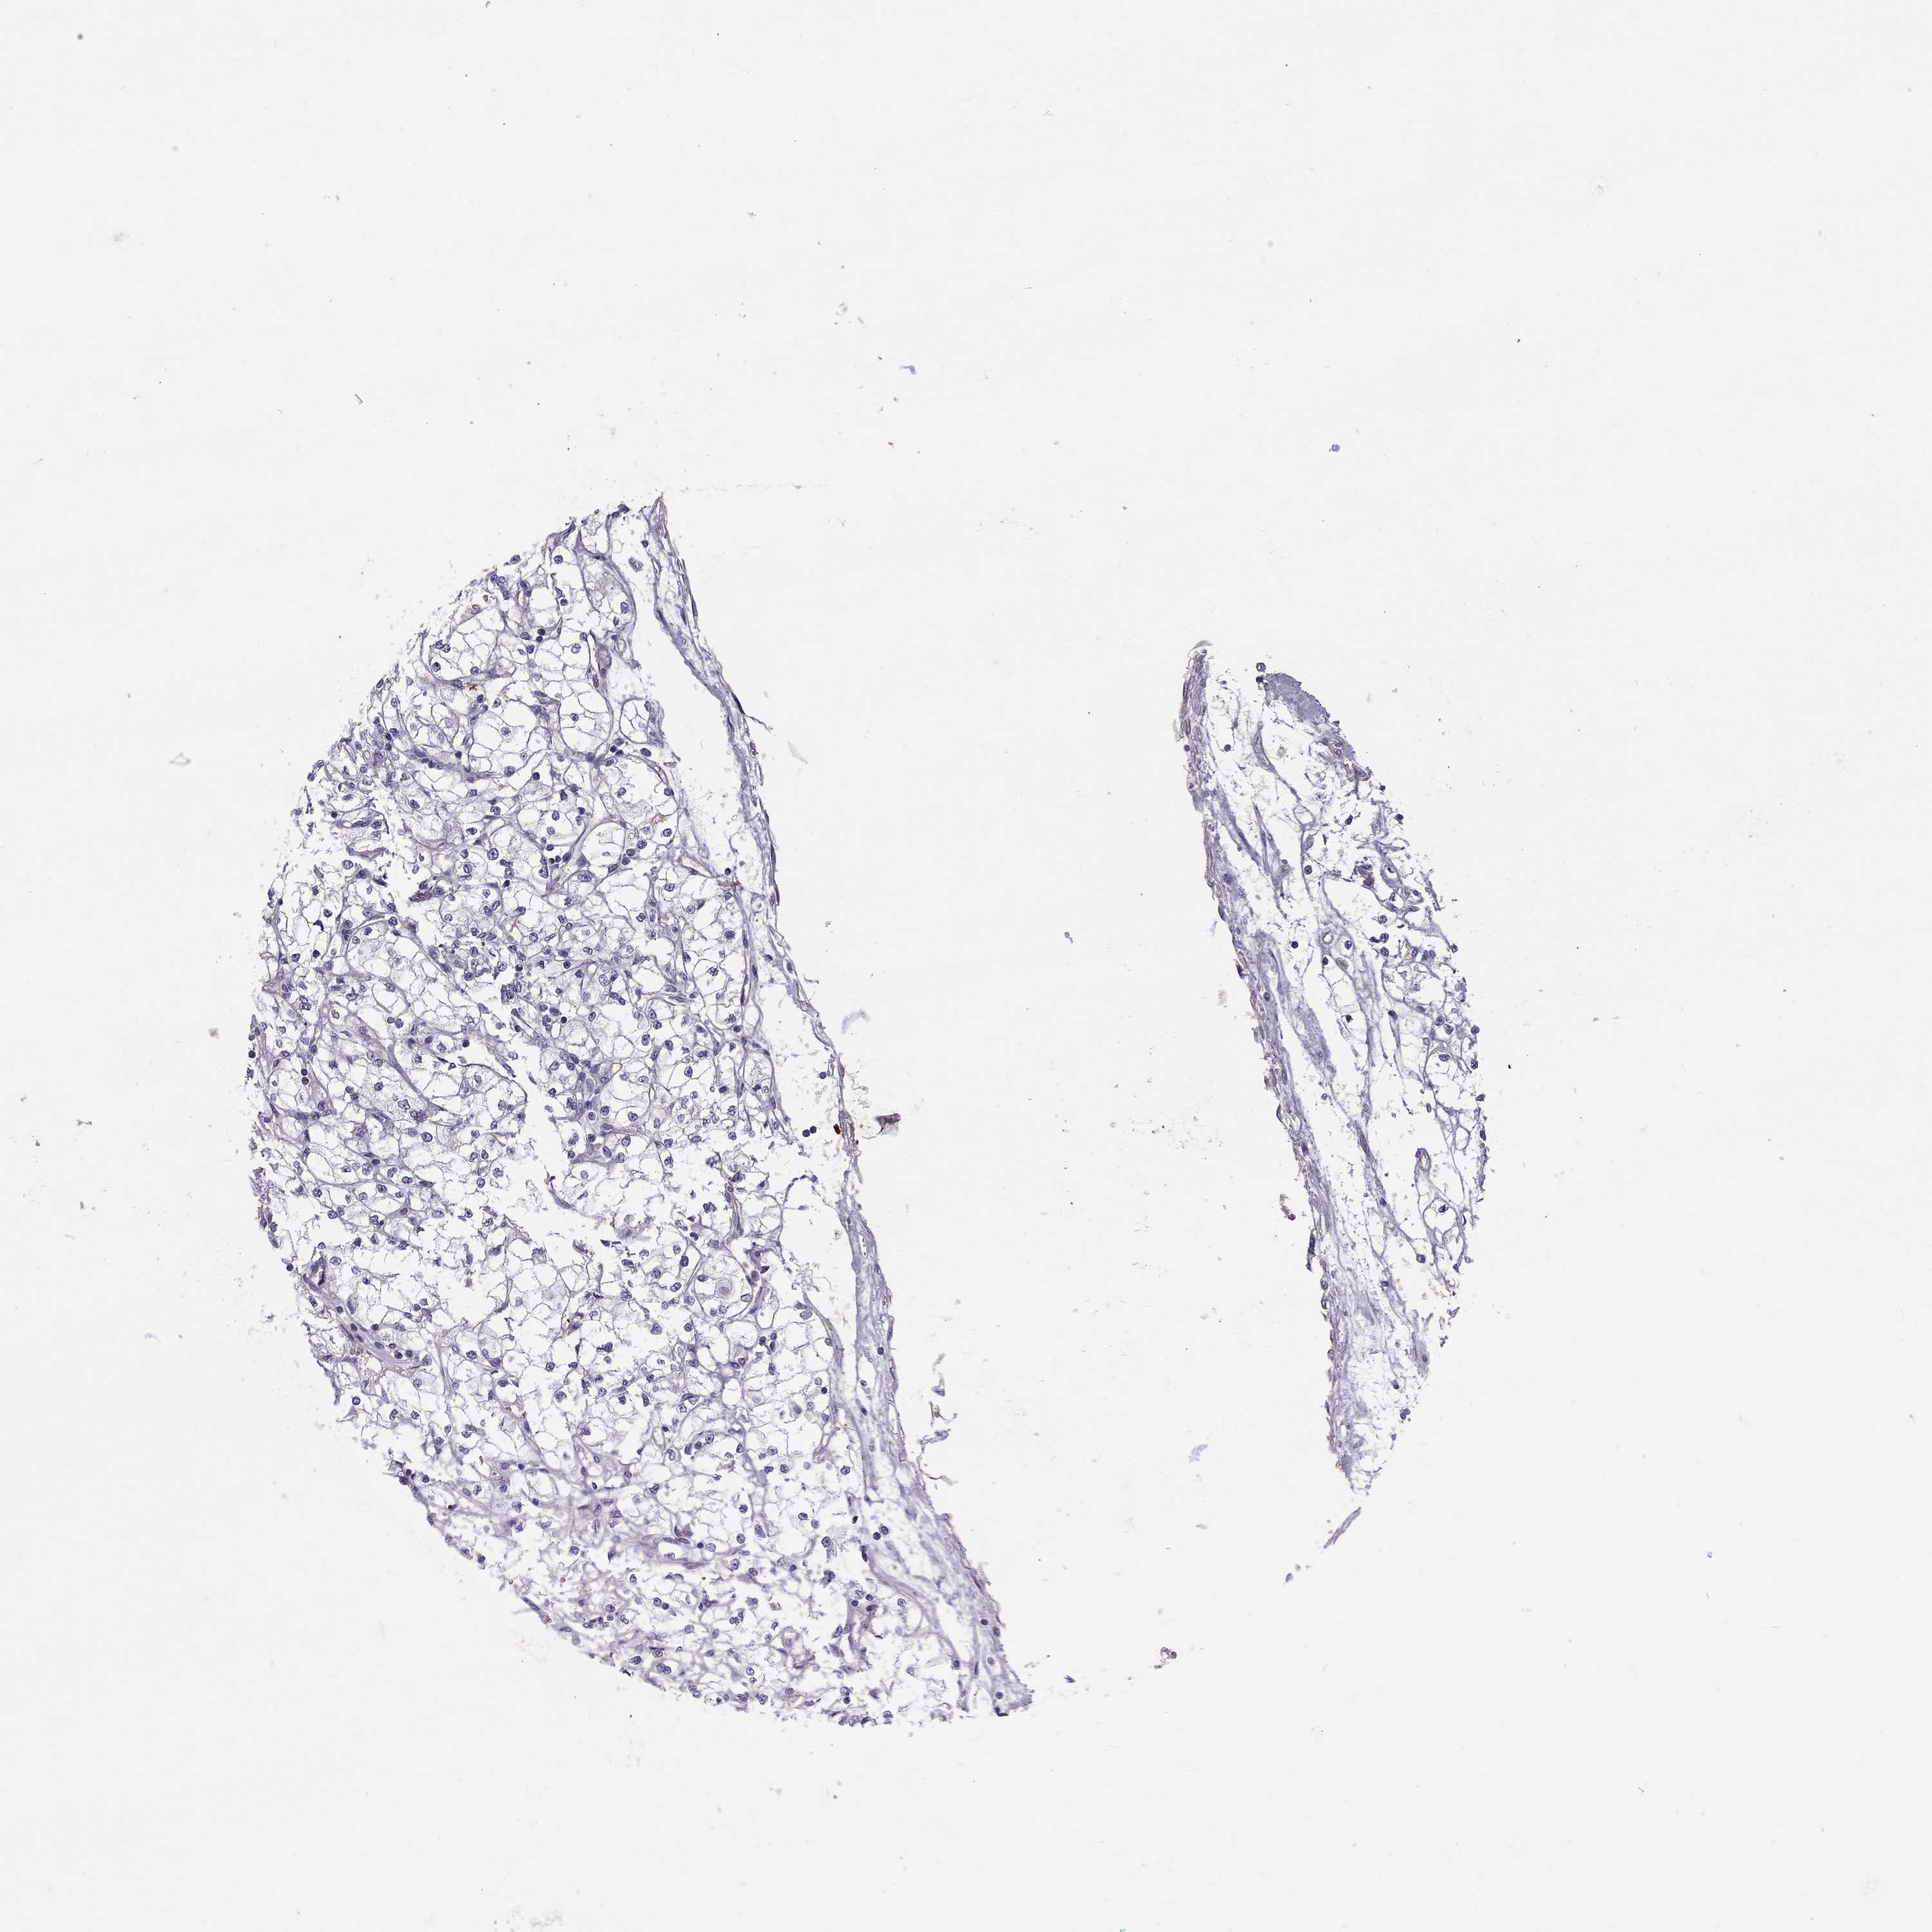

KIDNEY RENAL CLEAR CELL CARCINOMA (VALIDATION) - Interactive survival scatter ploti

The Survival Scatter plot shows the clinical status (i.e. dead or alive) for all individuals in the patient cohort, based on the same data that underlies the corresponding Kaplan-Meier plots. Patients that are alive at last time for follow-up are shown in blue and patients who have died during the study are shown in red.

The x-axis shows the expression levels (FPKM) of the investigated gene in the tumor tissue at the time of diagnosis. The y-axis shows the follow-up time after diagnosis (years). Both axes are complimented with kernel density curves demonstrating the data density over the axes. The top density plot shows the expression levels (FPKM) distribution among dead (red) and alive patients (blue). The right density plot shows the data density of the survived years of dead patients with high and low expression levels respectively, stratified using the cutoff indicated by the vertical dashed line through the Survival Scatter plot. This cutoff is automatically defined based on the FPKM cutoff that minimizes the p-score. The cutoff can be changed by dragging the vertical line or by entering a cutoff value in the square labeled "Current cut-off".

Under the Survival Scatter plot the p-score landscape (black curve; left axis) is shown together with dead median separation (red curve; right axis). Dead median separation is the difference in median mRNA expression between patients who have died with high and low expression, respectively. It is calculated as follows: median FPKM expression of dead patients with high expression - median FPKM expression of dead patients with low expression. This is intended to aid the user in visually exploring custom cutoffs and the associated p-scores and dead median separation.

Individual patient data is displayed and can be filtered by clicking on one or more of the category buttons on the top of the page. Categories describing expression level and patient information include: high, low, alive, dead, female, male and tumor stages. The scale of the x-axis can be toggled between linear and log-scale by clicking on the "x log" button. Mouse-over function shows TCGA ID, patient information and mRNA expression (FPKM) for each patient.

& Survival analysisi

Kaplan-Meier plots summarize results from analysis of correlation between mRNA expression level and patient survival. Patients were divided based on level of expression into one of the two groups "low" (under cut off) or "high" (over cut off). X-axis shows time for survival (years) and y-axis shows the probability of survival, where 1.0 corresponds to 100 percent.

TDRD6 is not prognostic in Kidney Renal Clear Cell Carcinoma (validation)

: 1.56

Average pTPM 2.2

Number of samples 100